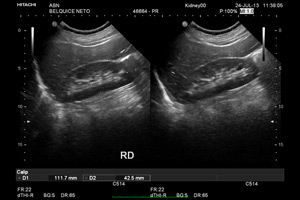

Ecografia

A ecografia é um método de diagnóstico por imagem usada para reproduzir imagens dos órgãos internos, tecidos, rede vascular e fluxo sanguíneo através do ultra-som.

O equipamento chamado de sonda envia ondas sonoras até á área a ser estudada, que as reflecte para o transdutor novamente e depois são convertidas em imagens bidimensionais. A captação dessas imagens são em tempo real, mostrando instantâneamente a posição dos órgãos internos e tecidos e o fluxo sanguíneo. A Ecografia é utilizada para o diagnóstico e acompanhamento de doenças e em procedimentos cirúrgicos.